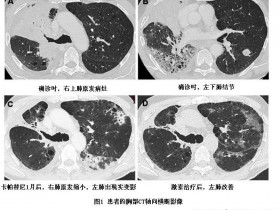

卡帕替尼(Capmatinib)INC280导致的间质性肺炎一例 新药资讯

卡帕替尼(Capmatinib)INC280导致的间质性肺炎一例

近期《毒理学与应用药理学》杂志报道了一例卡帕替尼(Capmatinib)INC280导致的间质性肺炎(DOI: 10.1016/j.cpccr.2020.100024)。   一位76岁法国男性,有吸...